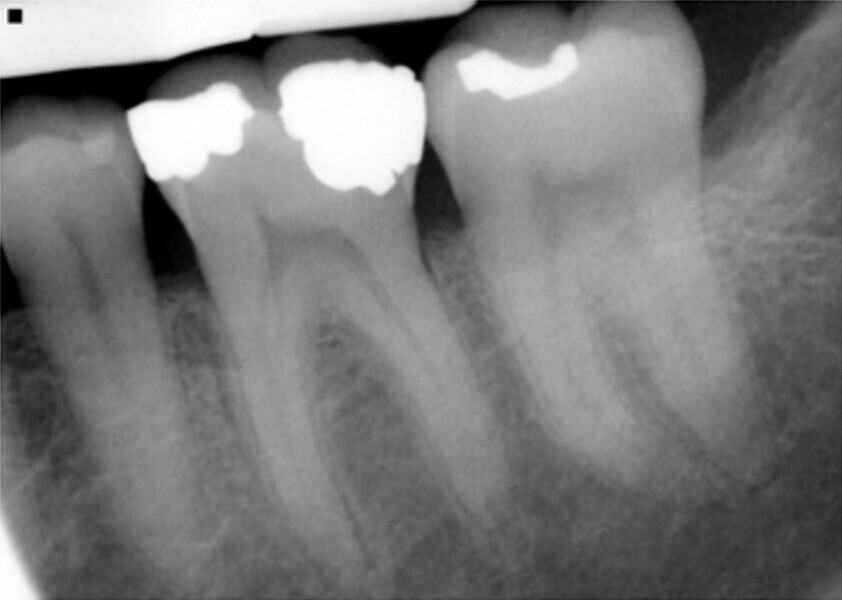

Fig. 14: Patient presented with complaint of pain on chewing on teeth 14 and 15 with increasing sensitivity to hot.

Fig. 15: Instrumentation performed with ExactTaperH DC files and obturation with a single cone of GP and Bioceramic Root Canal sealer completing endodontic treatment.